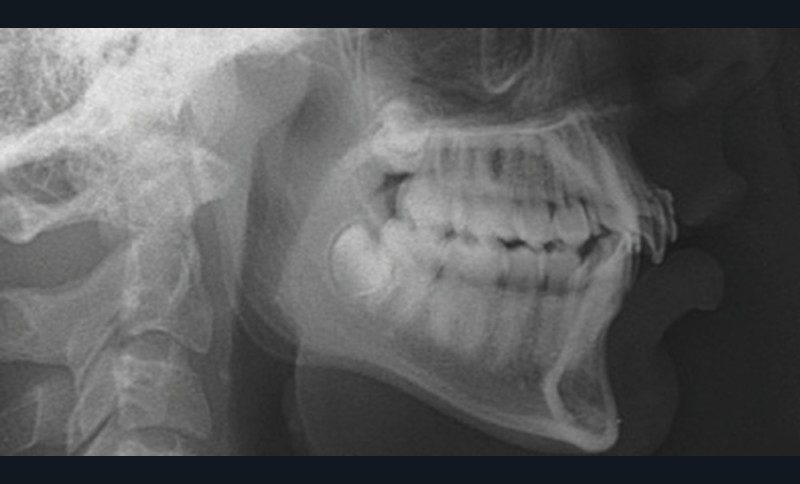

L’analyse de la téléradiographie de profil (fig. 1g) confirme une classe II squelettique à tendance hyperdivergente avec une normo-position de l’incisive mandibulaire dans sa symphyse. L’âge du patient et la croissance mandibulaire en rotation postérieure (travaux de Björk) ne permettront sans doute pas une correction de la classe II squelettique sans version de l’incisive mandibulaire.